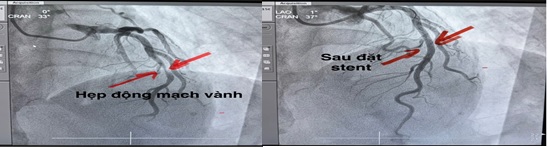

Ngay sau khi có chẩn đoán xác định, ê-kíp can thiệp tim mạch đã được kích hoạt. Bệnh nhân nhanh chóng được đưa lên phòng DSA để chụp và can thiệp động mạch vành. Kết quả chụp cho thấy nhánh động mạch liên thất trước bị tắc nghẽn đã được tái thông hoàn toàn bằng kỹ thuật đặt stent động mạch vành (khung giá đỡ kim loại). Sau can thiệp, bệnh nhân ổn định toàn trạng, đỡ đau ngực. Sáng ngày 16/2, Bệnh nhân sức khỏe ổn định đã được xuất viện về đón Tết cùng gia đình.